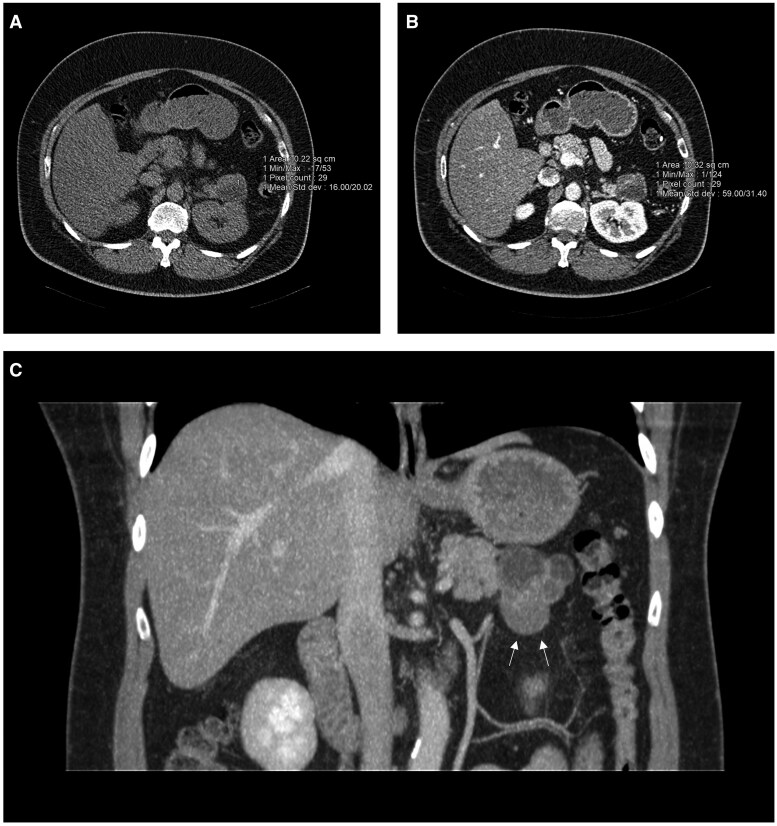

Pancreatic dermoid cyst is an extremely rare benign neoplasm of the pancreas. Pre-operative diagnosis is often difficult due to its rarity and overlapping features with other pancreatic cystic neoplasms. We report a case of a 55-year-old male with an incidental finding of a lobulated complex cystic lesion in the tail of the pancreas on imaging and the challenges to obtain a definitive diagnosis. Due to suspicious features on imaging and elevated CA 19-9 tumour marker, surgical resection was recommended at the Pancreatic Multidisciplinary Team Meeting. The patient subsequently underwent a distal pancreatectomy and splenectomy which confirmed a dermoid cyst.